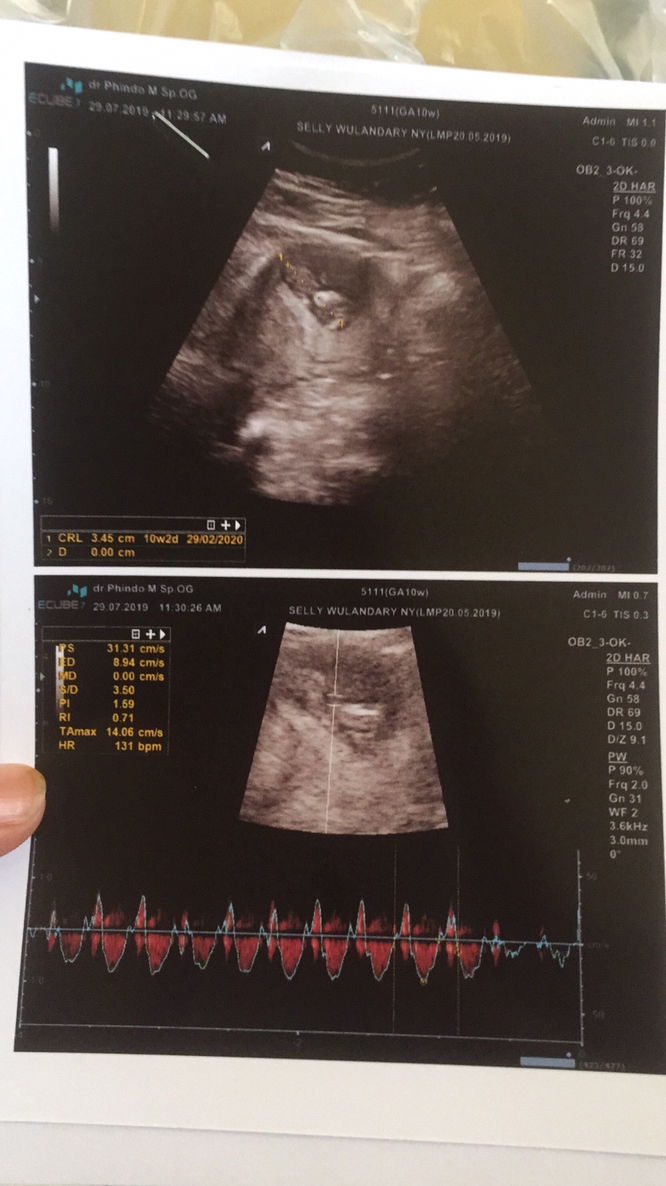

USG perdana

Hai bun cuma mau sharing kebahagian akhirnya setelah banyak membaca postingan bunda disini, banyak ketakutan dan kegelisahan yg saya alami. Banyak yg bilang lebih baik usg di usia 8 minggu, eh ketika saya memutuskan ingin usg di usia 8 minggu Saya kembali membaca satu komentar bunda bunda lagi ada yg bilang "sementara kalo ga ada flek atau keluhan lebih baik usg di usia 10week ke atas, takutnya nanti down ketika belum terdeteksi" Saya jadi makin takut lagi buat usg takut tidak sesuai harapan dan malah kecewa? Tapi setelah akhirnya menunggu dengan kesabaran dan kebimbangan serta penasaran yang luar biasa, Akhrinya saya memutuskan untuk USG perdana di usia 10 week Dan alhamdulillah wasyukurillah semuanya normal bun, Keparnoaan, kegelisahan, dan ketakutan saya sudah terjawab. Yang akhirnya berujung bahagia dan senang sekali mendengar detak jantung dan janinnya bun? Alhamdulillah